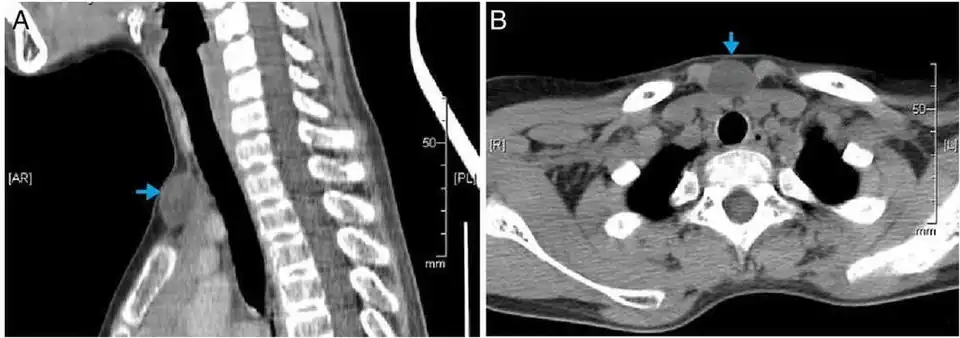

Scanner montrant une image hypodense homogène (kyste non spécifique)